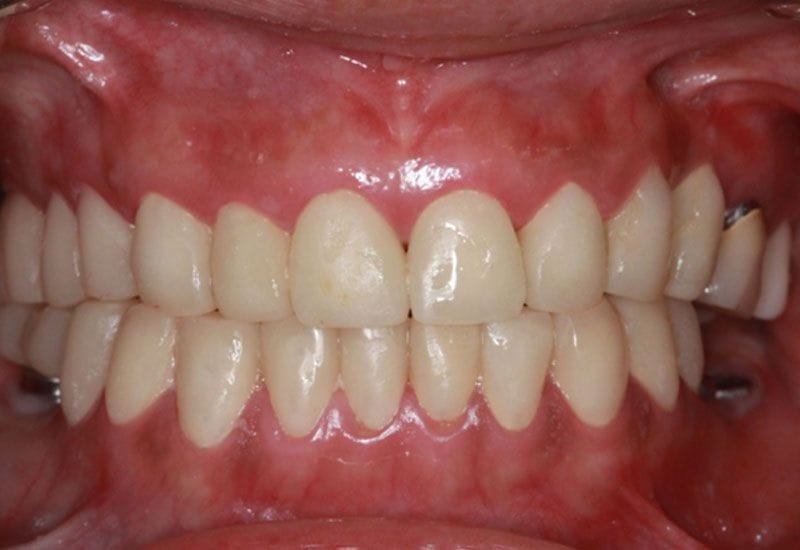

假牙完成後 病患恢復咬合功能,微笑曲線的建立與全瓷假牙的治療,讓病患有自信的笑容,牙齒也因為有了保護而減低敏感度,此後建議病患定期回診 並已製作咬合板 請病患於睡覺時配戴 防止夜間磨牙的高咬合力量造成假牙或牙齒的損害

如圖13.14

圖13

圖14